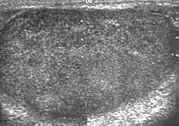

The normal adult testis is an ovoid structure measuring 3 cm in anterior-posterior dimension, 2–4 cm in width, and 3–5 cm in length. The weight of each testis normally ranges from 12.5 to 19 g. Both the sizes and weights of the testes normally decrease with age. At ultrasound, the normal testis has a homogeneous, medium-level, granular echotexture. The testicle is surrounded by a dense white fibrous capsule, the tunica albuginea, which is often not visualized in the absence of intrascrotal fluid. However, the tunica is often seen as an echogenic structure where it invaginates into the testis to form the mediastinum testis. In the testis, the seminiferous tubules converge to form the rete testes, which is located in the mediastinum testis. The rete testis connects to the epididymal head via the efferent ductules. The epididymis is located posterolateral to the testis and measures 6–7 cm in length. At sonography, the epididymis is normally iso- or slightly hyperechoic to the normal testis and its echo texture may be coarser. The head is the largest and most easily identified portion of the epididymis. It is located superolateral to the upper pole of the testicle and is often seen on paramedian views of the testis. The normal epididymal body and tail are smaller and more variable in position.